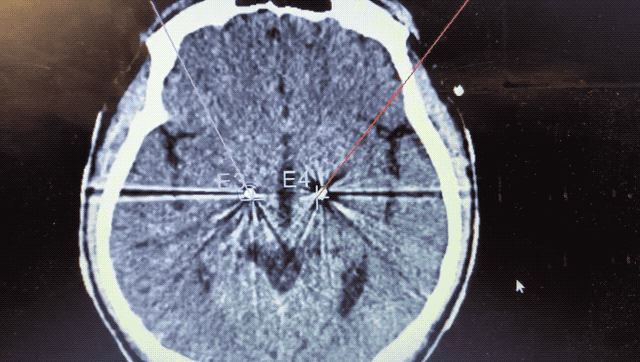

術(shù)中監(jiān)測到典型核團信號

順利檢測到典型的核團信號后,再次植入刺激電極到相應(yīng)位置,測試后即可完成單側(cè)的電極植入。對側(cè)只需借助機器人再次定位,并將檢測電極、刺激電極依次植入,最后,還需將刺激器植入患者胸前皮下。根據(jù)術(shù)后CT顯示,本手術(shù)雙側(cè)植入電極的位置與術(shù)前規(guī)劃路徑完全吻合,患者開機后,起搏器會開始沿刺激電極向患者核團實施高頻電刺激,以減輕疾病癥狀,提高患者的生活質(zhì)量。

術(shù)后CT顯示雙側(cè)電極植入位置與規(guī)劃完全吻合